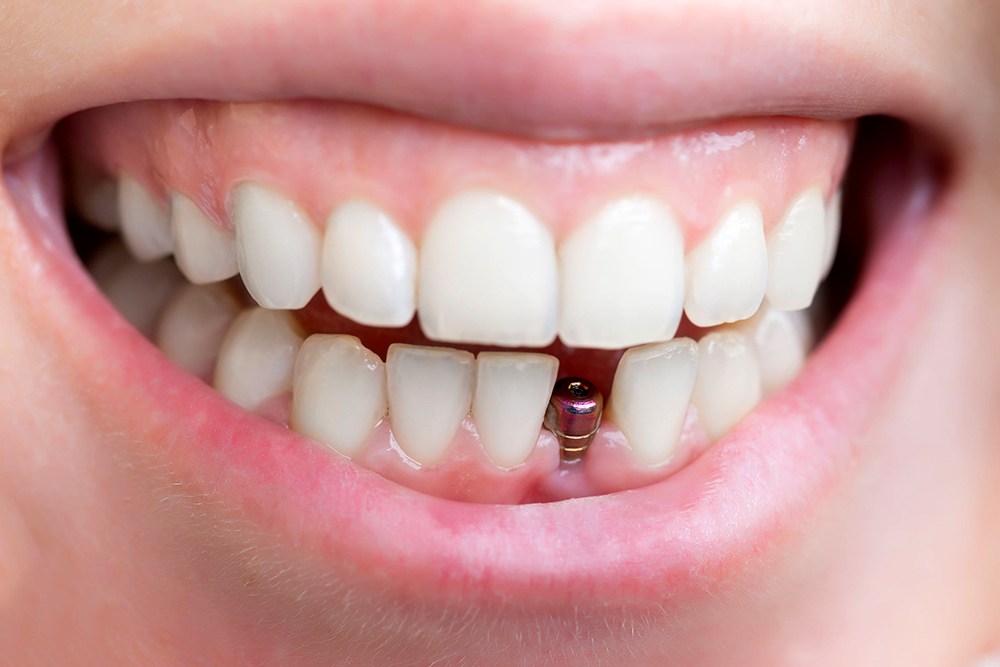

Cấy implant là phương pháp trồng răng tốt nhất hiện nay. Implant gồm có 3 phần, phần thứ nhất là chân răng, được cấy thẳng vào xương hàm thay thế chân răng mất. Phần thứ 2 là trụ phục hình abutment đó là phần kết nối với chân răng và nhô lên khỏi lợi để răng sứ bọc lên đó. Phần thứ 3 là răng sứ, sẽ là 1 chụp sứ hoặc hàm giả gắn lên abutment.

Khi mất một răng cửa bạn có thể lựa chọn các giải pháp phục hồi lại như làm hàm giả tháo lắp, làm cầu răng sứ, hoặc cấy chân implant. Trong đó cấy chân răng implant là giải pháp tốt nhất, bạn sẽ không phải can thiệp bào mòn 2 răng bên cạnh. Implant cũng ngăn ngừa được hiện tượng tiêu xương tiến triển khi mất răng.

Về định nghĩa chúng ta có thể hình dung implant là 1 vít (chân răng nhân tạo) làm bằng chất liệu titanium (có tính tương hợp sinh học với cơ thể người) được cấy vào xương để thay thế chân răng mất, nhằm nâng đỡ phục hình răng sứ. Như vậy bản chất của quá trình thực hiện implant chính là cấy ghép trên cơ thể người, chính vì vậy để sử dụng được loại răng này cần có một thời gian nhất định cho vít implant ổn định trong xương hàm, thời gian trung bình cho quá trình là khoảng 3 tháng, tuy nhiên vấn đề còn phụ thuộc nhiều yếu tố chuyên môn khác nữa.